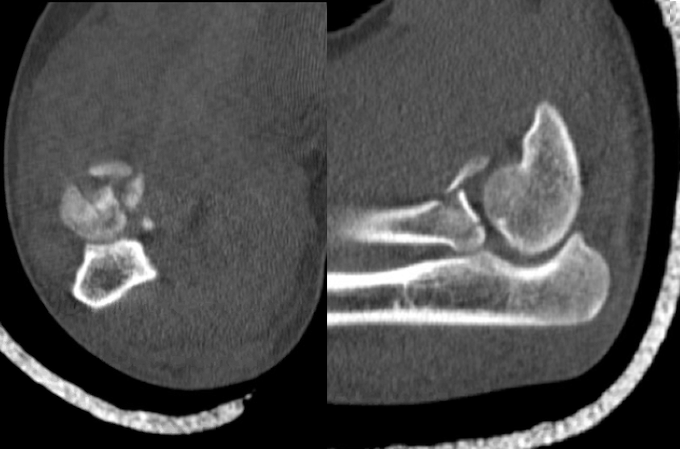

- The terrible triad injury (TTI) of the elbow involves a radial head fracture combined with an elbow dislocation and ulnar coronoid process fracture. This injury has earned its nickname because it is very challenging to treat successfully.13,15

Imaging

- Radiology studies - Computerized tomography (CT) scanning